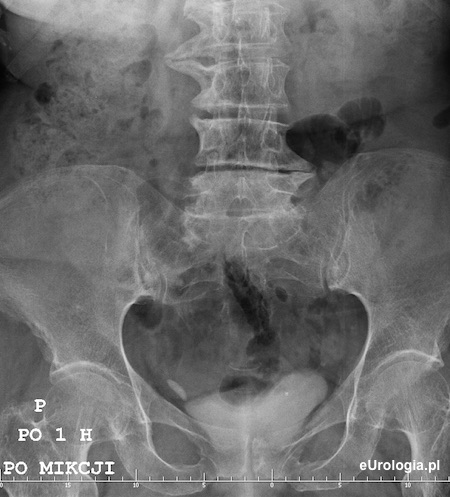

Zdjęcie wykonane godzinę po mikcji - zakontrastowany mocz w pęcherzu moczowym. Cień wapienny 20x10 mm będący złogiem w dolnym odcinku prawego moczowodu.